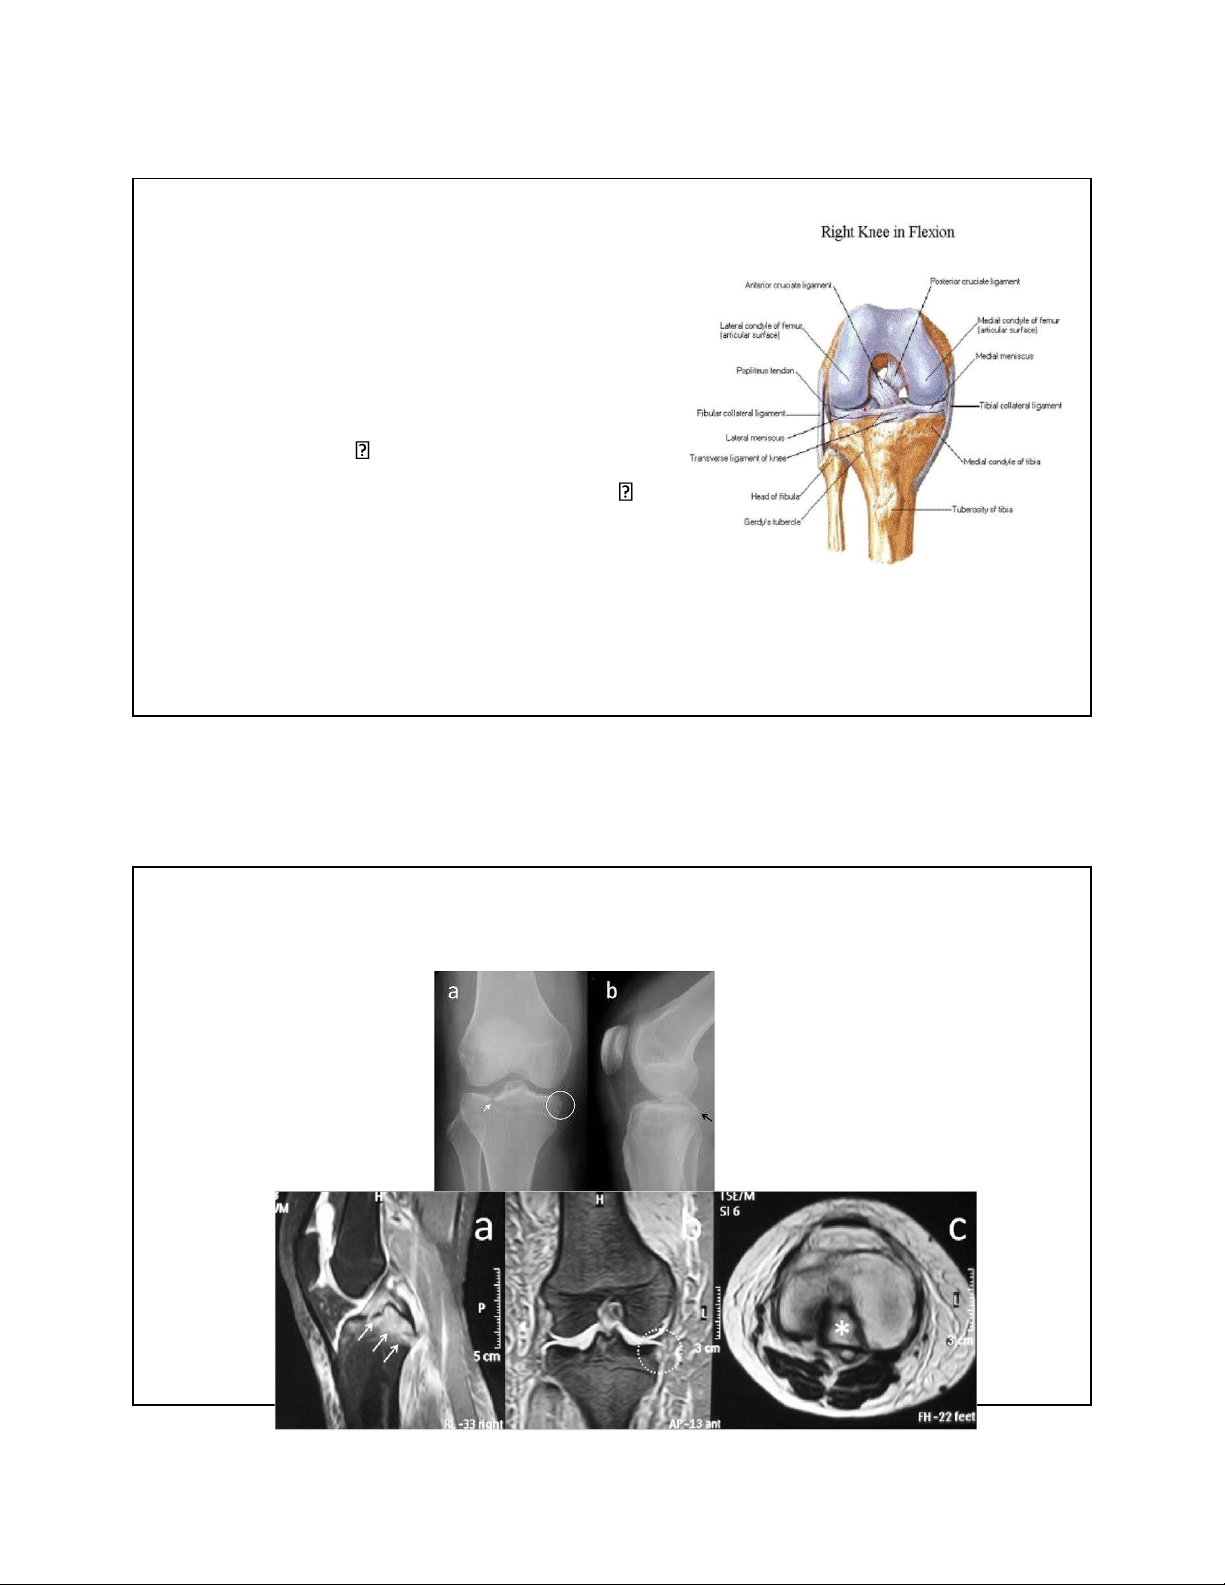

2. RÁCH SỤN CHÊM – CẮT LỌC SỤN CHÊM 10 lOMoAR cPSD| 22014077 7/15/2023 3. TỔN THƯƠNG DÂY CHẰNG

• Cấu trúc phức tạp nhất của khớp gối

• Tổn thương dây chằng ít gây au

• Tổn thương DC bên trong, bên ngoài,

tại chỗ bám ấn au iểm tổn thương

• Bong chỗ bám là 1 dạng gãy xương au nhiều

• XQ qui ước, CT, MRI có giá trị chẩn oán ầy rất tốt 11